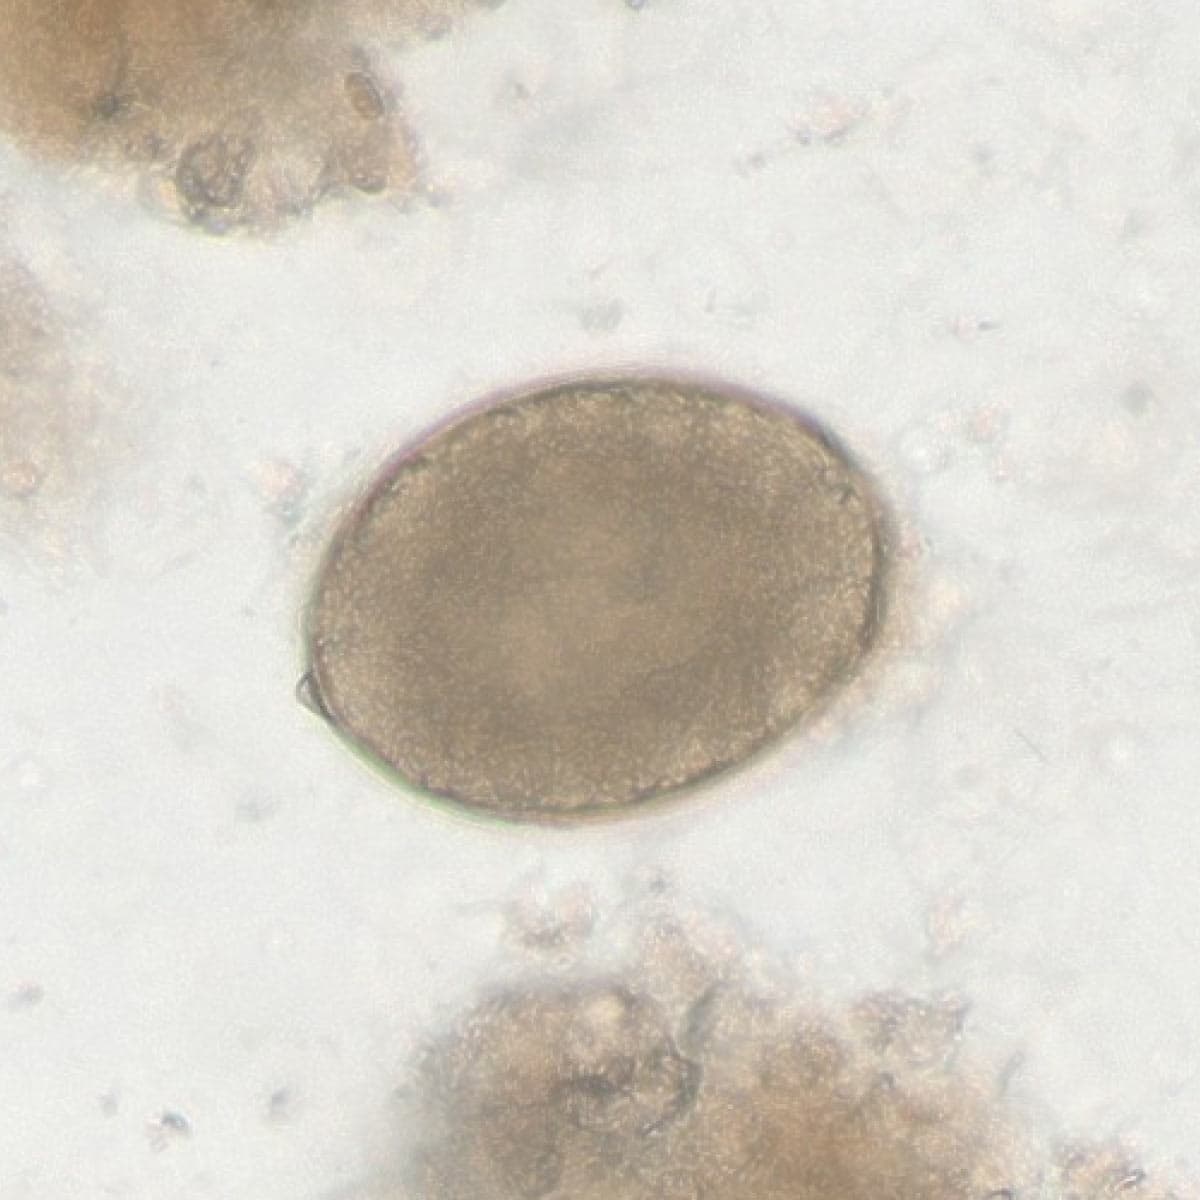

Automatic detection of rare species

Built on worldwide parasite-positive specimens, ParaScout AI identifies a vast number of parasite species, including those that are clinically rare or challenging to find.

Once the data is uploaded, the AI instantly identifies parasite species. You receive visual evidence for every finding, with dimensions to confirm the identification. Simply review the AI’s results and provide the final diagnostic confirmation.